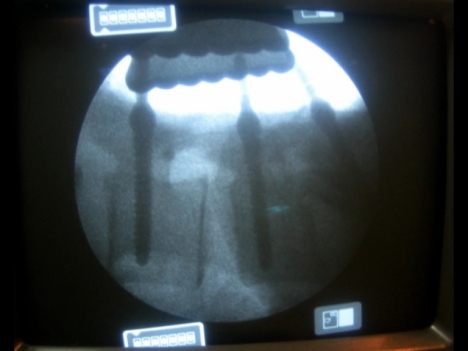

Foto 6

Estenosis lumbar

en la radiografía realizada durante la intervención se verifica que están introducidos correctamente.